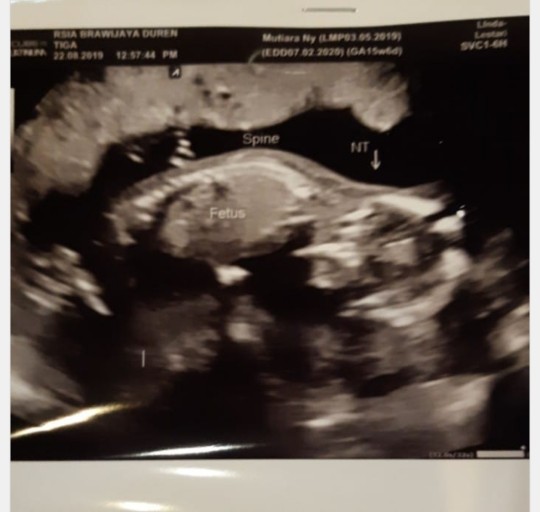

Pas USG 15 week posisi bayi saya juga kaya sujud kata dokter, begini bun... muka nya menghadap ke bawah